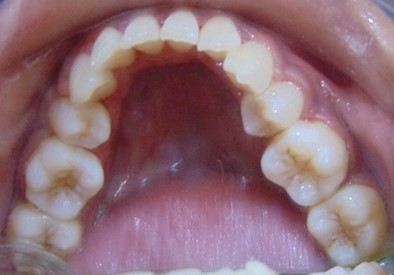

Divya Patil, 28Y, Duration - 6Months

Before

After

Image 1